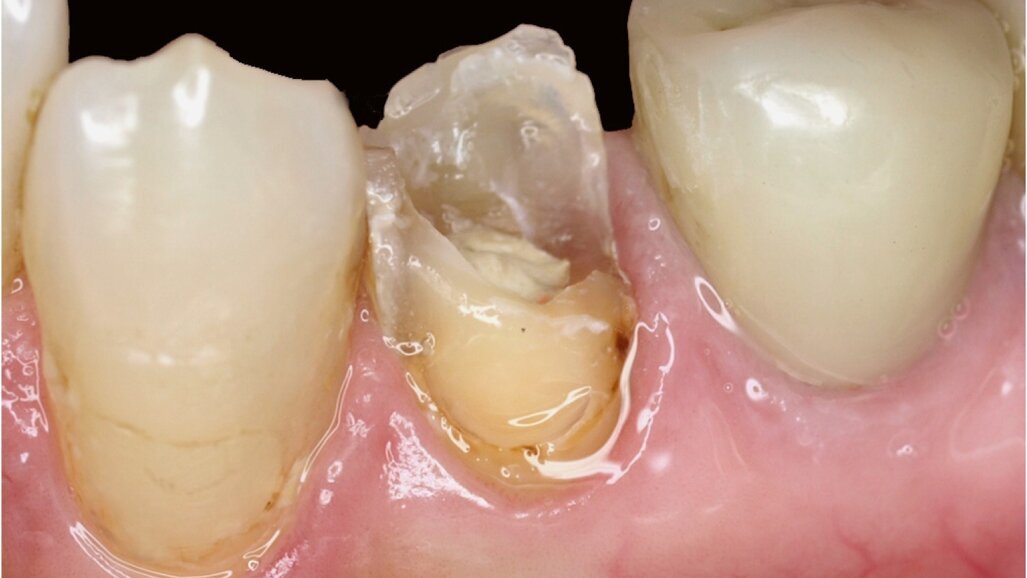

Figura 2. Situación de partida: pérdida acusada de sustancia en el diente 35 en la zona visible.

Figura 3. Situación de partida en el diente 35 desde coronal.

En el presente caso, el paciente se presentó con una pérdida acusada de sustancia en el diente 35 (Figuras 1-3). La preparación a modo de abrazadera o ferrule necesaria para una reconstrucción de espiga colada habría debilitado aún más la sustancia dental. Teniendo en cuenta la carga prevista sobre el muñón, se consideró insuficiente un anclaje de espiga puramente retentivo conforme al modelo tradicional. Así pues, en este caso se optó por la reconstrucción de espiga directa utilizando la técnica adhesiva. Además, la utilización de sistemas basados en la técnica adhesiva posibilita un procedimiento mínimamente invasivo, que conserva la sustancia dental y la aprovecha para la unión adhesiva.